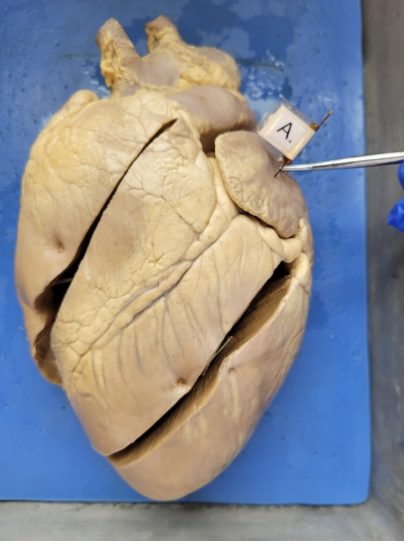

what is this

the left atrium

what is this

right ventricle

what is this

Aorta

what is this

the left ventricle

what is this

pulmonary artery

what is this

pulmonary vein